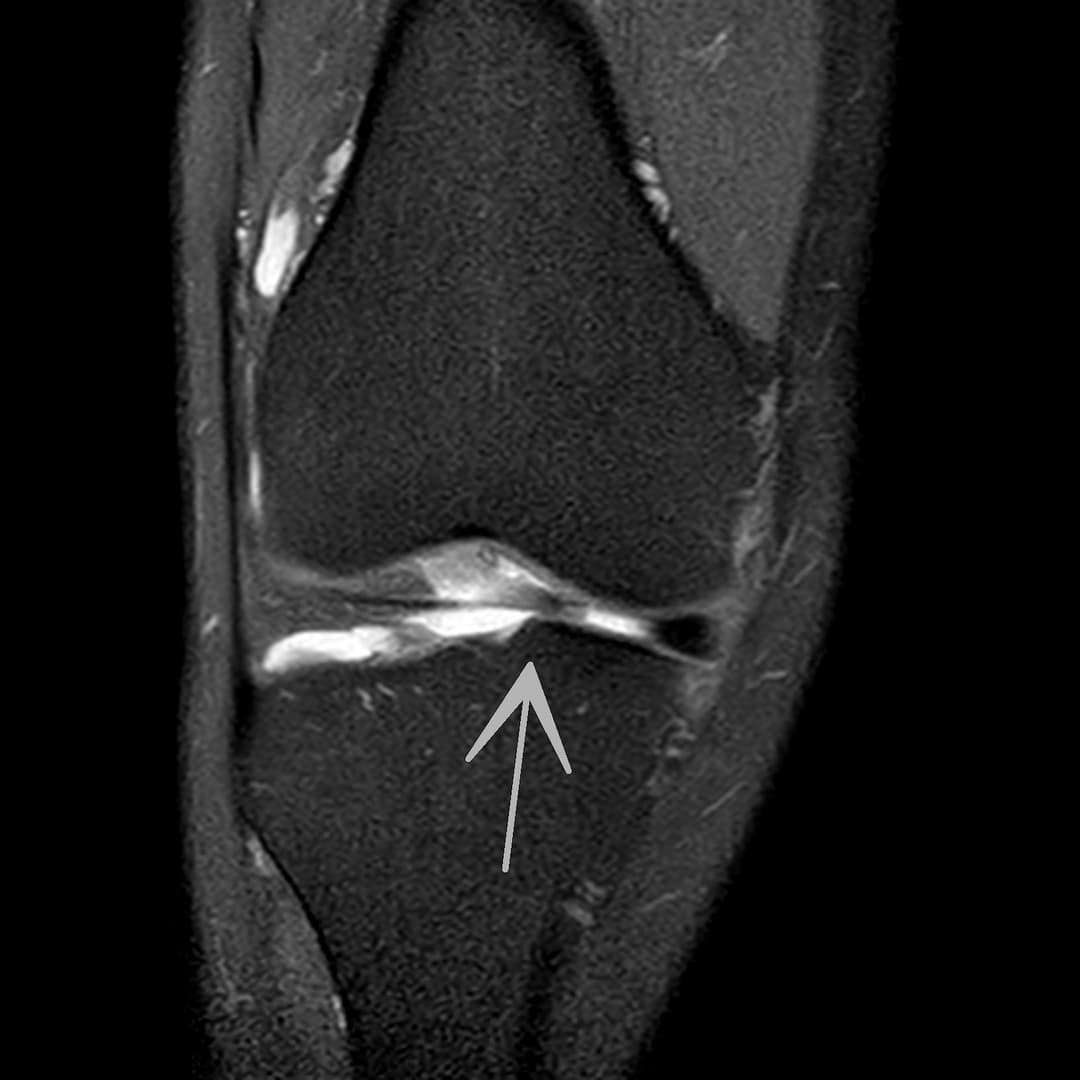

Languette méniscale instable

Languette méniscale rattachée à la corne antérieure du ménisque médial avec aspect flottant sur le versant antérieur de l'échancrure.